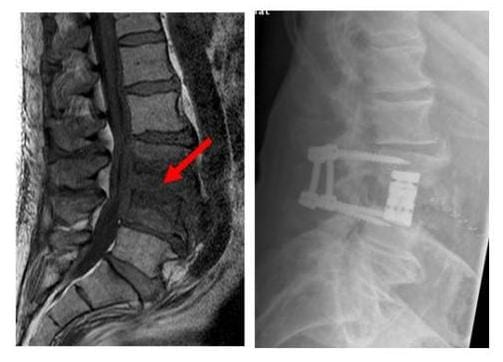

OPERATION BEI SPONDYLODISZITIS

Das Röntgenbild zeigt die ausgedehnte Infektion der Bandscheibe und angrenzenden Knochen das infizierte Gewebe wurde entfernt und die Wirbelsäule mit einem Doppelstabsystem und einem Cage stabilisiert

Das MRT (links) zeigt die ausgedehnte Infektion der Bandscheibe und angrenzenden Knochen (roter Pfeil). Das infizierte Gewebe wurde entfernt und die Wirbelsäule mit einem Doppelstabsystem und einem Cage stabilisiert (rechtes Bild). (Bilder: Orthopädie)